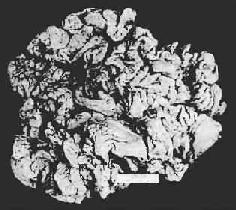

胃粘膜肠上皮化生

图10-4 胃粘膜肠上皮化生

胃粘膜上皮出现多量充满粘液的杯状细胞